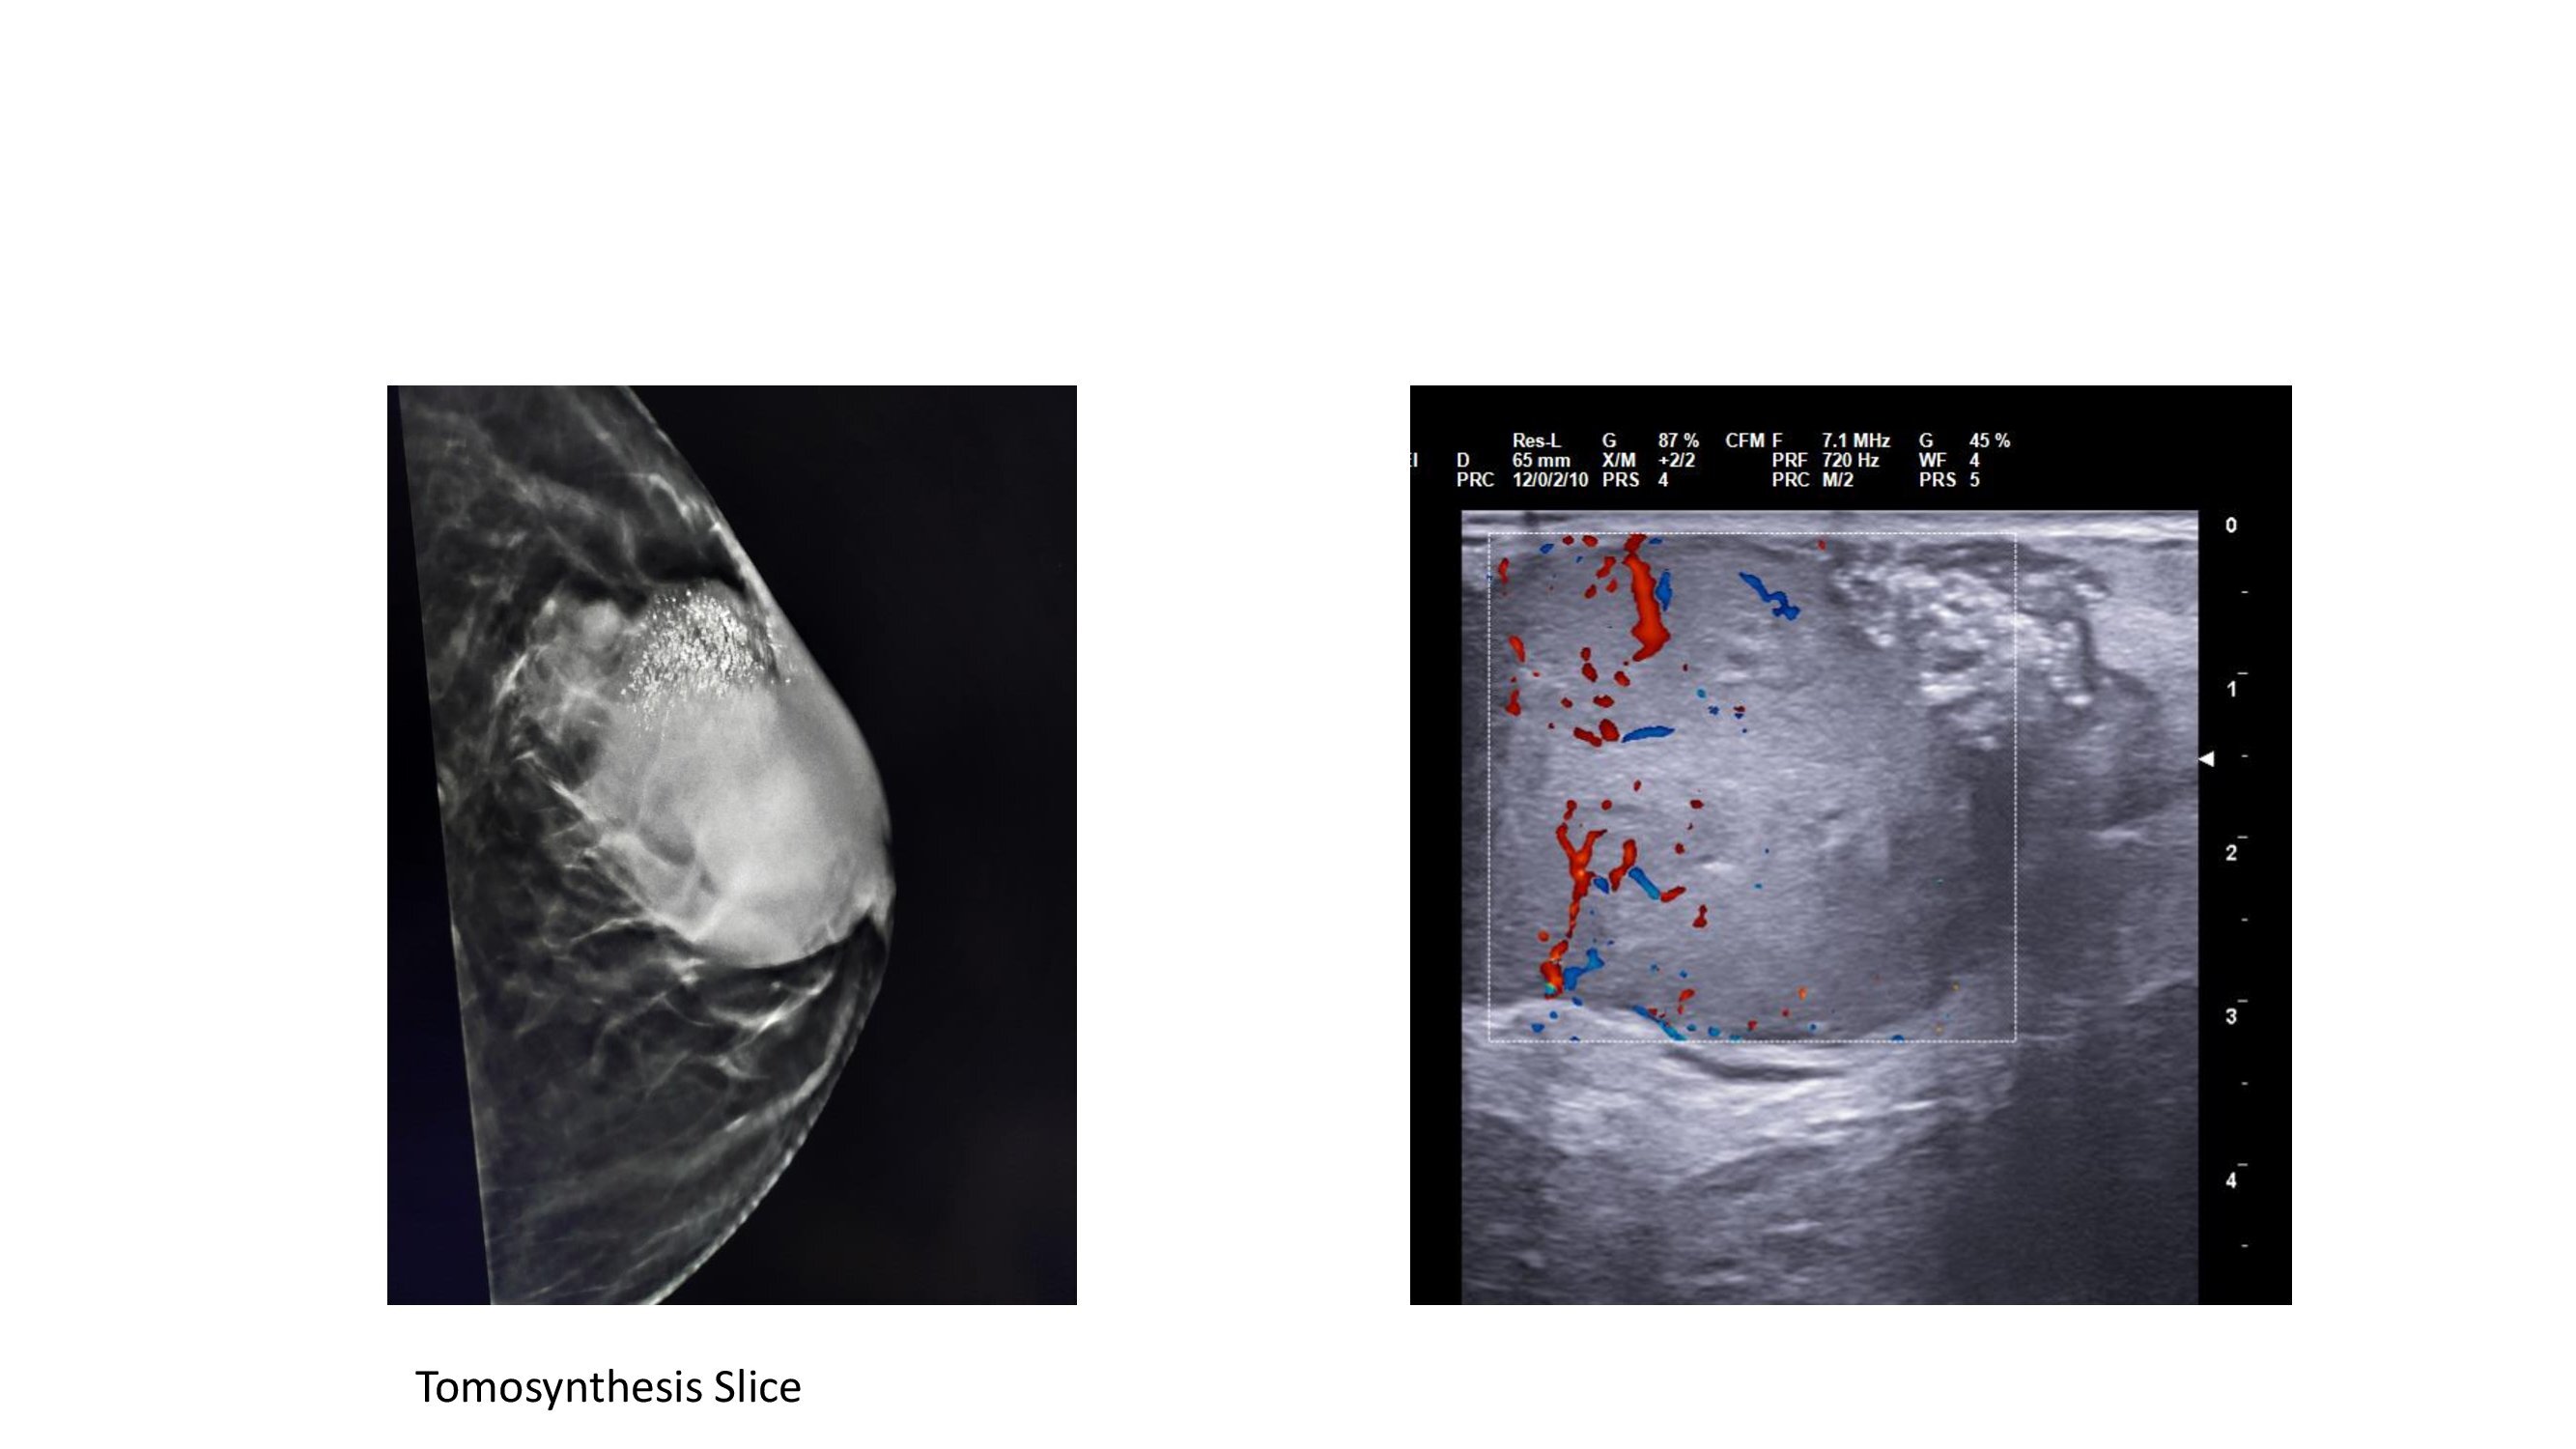

A circumscribed high density lesion ( size 4.5x5.5x6cm) is noted in the upper outer quadrant extending to the retroareolar region . On tomosynthesis, irregular margins were seen. There are fine pleomorphic microcalcifications in the lesion. The lesion is abutting the overlying skin. The skin is thickened and the nipple is retracted. The left axilla shows 2-3 lymph nodes with thickened cortex. On USG the mass was iso to hypechoic with irregular circumscribed margins with increased vascularity.There are mixed posterior features. Microcalcifications were seen in the upper outer region of the mass. BIRADS 5 was assigned for the lesion and USG guided biopsy was recommended. USG guided FNAC from the left axillary node showed only reactive lymphoid hyperplasia. USG guided core biopsy showed Invasive breast cancer NST, Nottingham Grade II. Immunohistochemistry report is awaited.